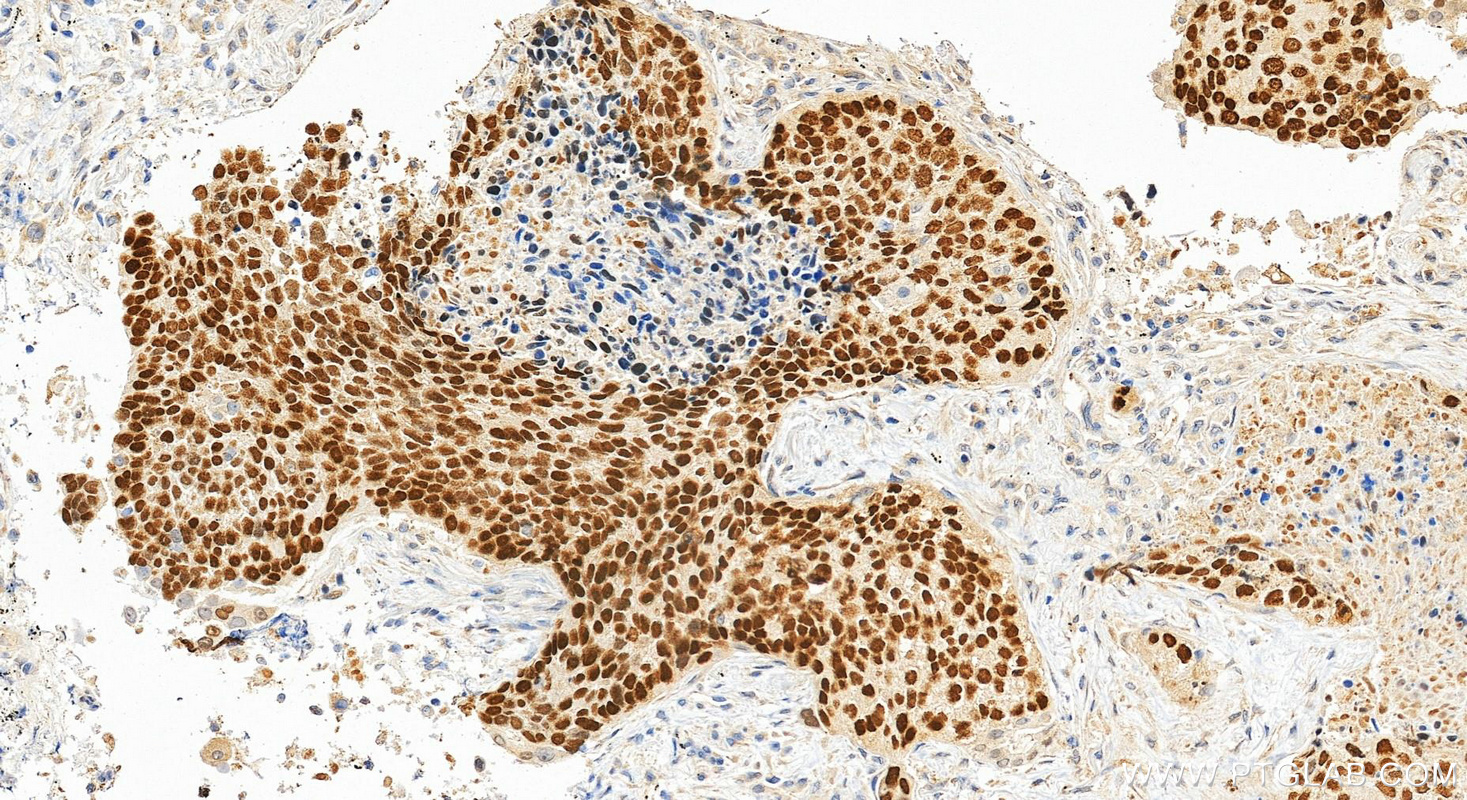

| Positive IHC detected in | human lung cancer tissue, human bowen disease tissue, human prostate cancer tissue, human tonsillitis tissue Note: suggested antigen retrieval with TE buffer pH 9.0; (*) Alternatively, antigen retrieval may be performed with citrate buffer pH 6.0 |

12143-1-AP targets p63 in WB, IHC, IF/ICC, IF-P, FC (Intra), IP, CoIP, ChIP, ELISA applications and shows reactivity with human, mouse, rat samples.

| 经测试应用 | WB, IHC, IF/ICC, IF-P, FC (Intra), IP, ELISA Application Description |

TP63, also named KET, P63, P73H, P73L and TP73L, belongs to the p53 family. It is a homologue of the tumor suppressor p53 and p73 genes. It is involved in malignancy acquisition and maintenance of cells. Unlike p53, the p63 gene encodes multiple isotypes with remarkably divergent abilities to transactivate p53 reporter genes and induce apoptosis. TP63 acts as a sequence specific DNA binding transcriptional activator or repressor. TP63 has 12 isoforms with MW 40kd(P40), 50kd(P60),63kd(P63) and 73kd(P73L).